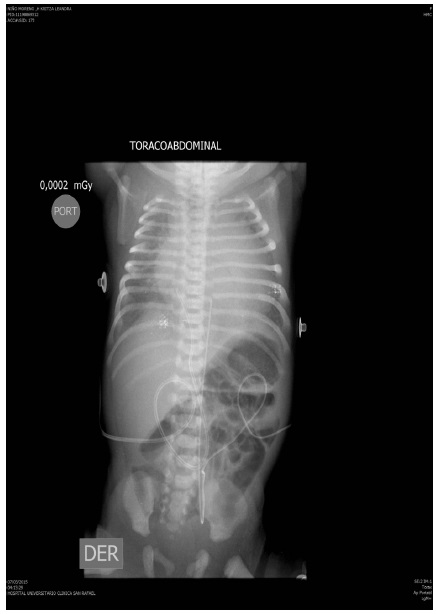

En salas de cirugía se obtiene recién nacida vigorosa, con peso y talla adecuados para la edad gestacional; Ballard de 38 semanas, con adecuada adaptación neonatal a pesar de presentar frecuencia cardiaca de 50 lpm. Inicialmente sin signos de bajo gasto o de dificultad respiratoria. Aproximadamente a las 12 horas de vida la recién nacida presenta dificultad respiratoria, llenado capilar lento con tendencia a la hipotensión arterial, por lo cual se decide iniciar ventilación mecánica invasiva; se intenta mejorar la frecuencia cardiaca con medidas farmacológicas, sin respuesta de la paciente; se toma radiografía de tórax (figura 3) que muestra cardiomegalia. Se informa a cirugía cardiovascular quienes realizan implantación de marcapasos programado epicárdico unicameral ventricular, con frecuencia cardiaca de 120 lpm y umbral de 0,9. Posterior a la cirugía la recién nacida es trasladada a la unidad de cuidados intensivos pediátricos para continuar manejo integral. En el ecocardiograma de control se evidencia marcapasos unicameral de demanda ventricular (VVI), con un corazón estructuralmente sano y adecuada función biventricular. La evolución de la recién nacida al año de vida ha sido satisfactoria, con adecuado desarrollo neurológico y ponderal.